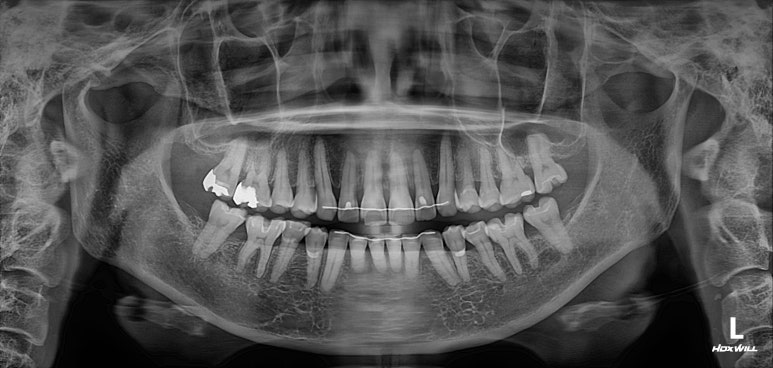

엑스레이를 찍는 이유는 잇몸이 건강한지를 확인하기 위함입니다.

50대 여성분임에도 불구하고 충분히 건강한 잇몸상태를 확인할 수 있었습니다.

그러면.. 교정치료가 가능하다는 뜻입니다.

치아의 뿌리 상태를 확인하기 위한 방사선 사진 촬영 필수!

교정을 하기 전에 무조건 위아래 앞니의 뿌리길이를 체크해야 합니다.

아무래도.. 성인교정의 대부분은 삐뚤어진 앞니 배열의 개선이지요?

그러면 앞니의 움직임이 다소 많을 것이기 때문에, 교정하기에 적합한 뿌리 길이를 갖고 있는지 확인해야합니다.

그런 면에서 이번 환자분은 당연히 합격!

마지막으로 파노라마 엑스레이를 찍고 마무리하였습니다.

보시다시피 모든 치아가 뿌리가 나란하게끔 교정이 마무리 된 것은 아닙니다만, 생리적으로 적절한 교합을 형성하였고 가장 눈에띄는 앞니는 배열을 가지런히 맞추어 내었습니다.

치과용 파노라마 엑스레이를 보았을 때, 특별히 잇몸이 안좋아진 치아도 보이지 않았으며 향상된 치아배열로 인해 구강위생관리 또한 향상되어 있다는 생각이 절로 들었습니다.